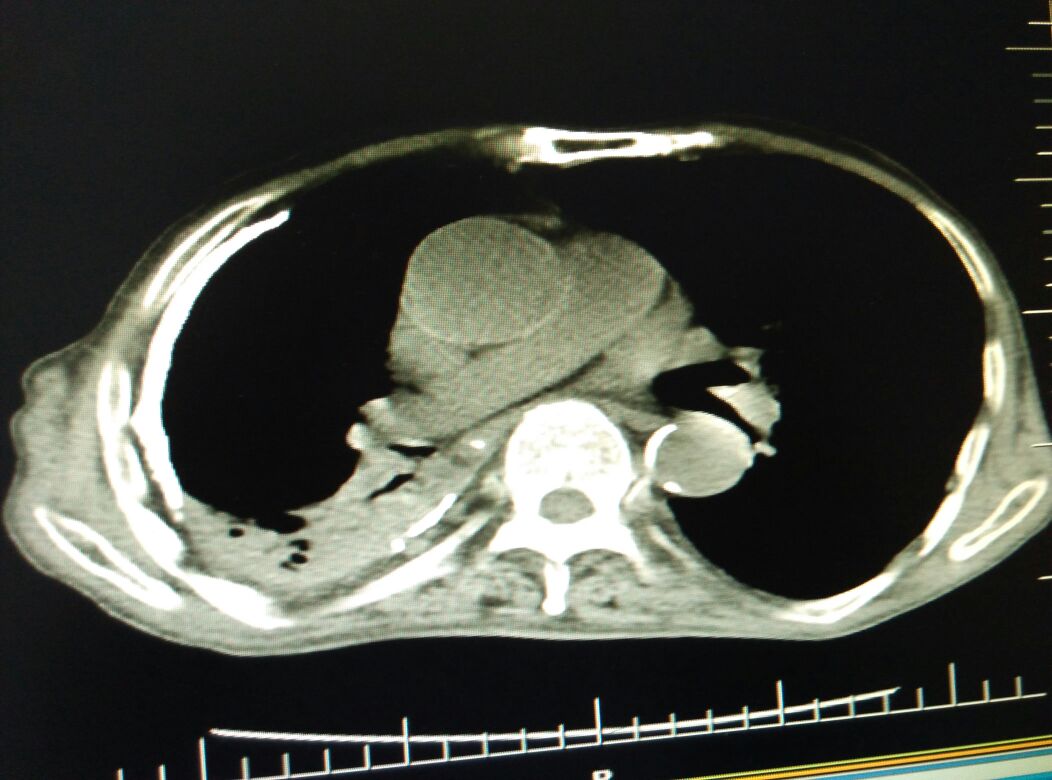

慢阻肺